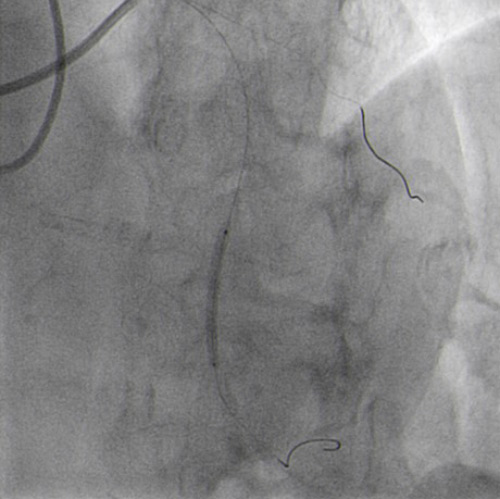

JR 4.0 guiding catheter exchanged with JL 4.0 to achieve left main (ping-pong) and position a parallel wire in left anterior descending (Figure 7.2). In the first wire we have the balloon, in the second wire a covered stent, but the perforation resolved only with balloon dilatation so we avoided, at this time to implant a covered stent.

JR 4.0 guiding catheter exchanged with JL 4.0 to achieve left main ping-pong (Figure 7.2).

After several minutes no contrast protrusion, the perforation appeared resolved, so the second wire in the JL catheter was removed and PCI completed with another DES implantation in proximal LAD (Figure 8.1).